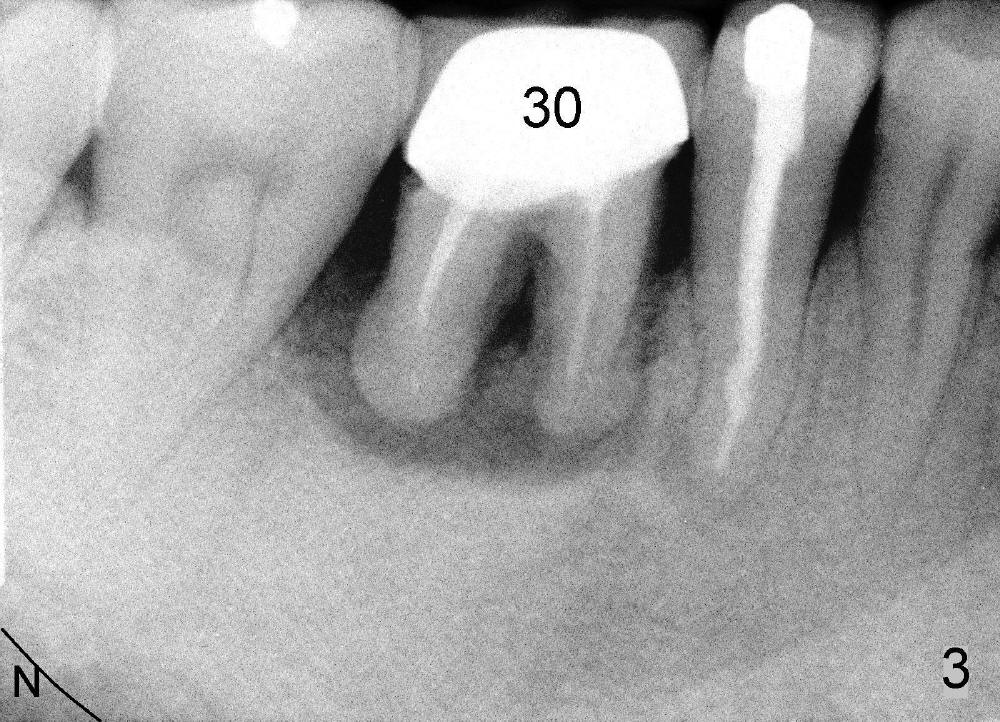

Regular posterior periapical (PA) device has a horizontal bite block (Fig.1: B). The latter rests on the occlusal surface of the posterior teeth to be taken radigraphically (Fig.2 illustration: yellow rectangle). This typical PA image shows the whole teeth including the crowns and the roots, but it does not catch the whole image of the inferior alveolar nerve as related to implant placement (Fig.3 N). The tooth #30 has complex endo-perio disease and is going to be extracted and restored by an implant.